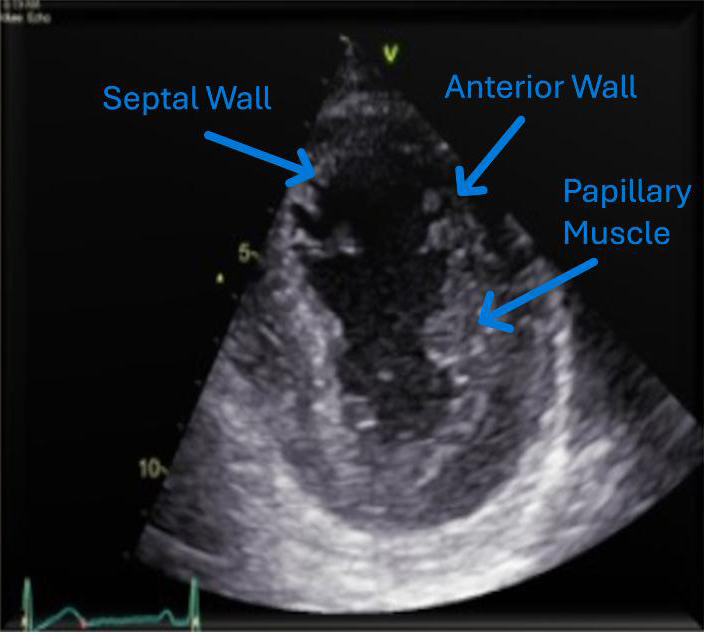

A young man in his early thirties, with a significant medical history of insulin-dependent diabetes mellitus (diagnosed 23 years prior) and ulcerative colitis (diagnosed one year prior), was admitted due to an acute flare-up of ulcerative colitis, characterised by frequent bloody stools and abdominal pain. Despite the initiation of intravenous steroids by the gastroenterology team, he developed symptoms indicative of AMI five days later, confirmed by ST-elevation in the anterior electrocardiogram (ECG) leads (figure 1), and a significant rise in troponin levels, peaking at over 25,000 ng/L. Cardiac echocardiography revealed akinesia of apex, apical inferoseptal and mid-to-apical anteroseptal walls with mildly impaired left ventricular systolic function (figures 2 and 3). Noteworthy was the absence of obstructive atherosclerotic coronary disease in major epicardial vessels, apart from atherothrombotic occlusion in the left anterior descending (figure 4) and diagonal arteries (figure 5), which was addressed with thrombectomy via export catheter, a drug-eluting balloon and intravenous glycoprotein IIb/IIIa inhibitor.